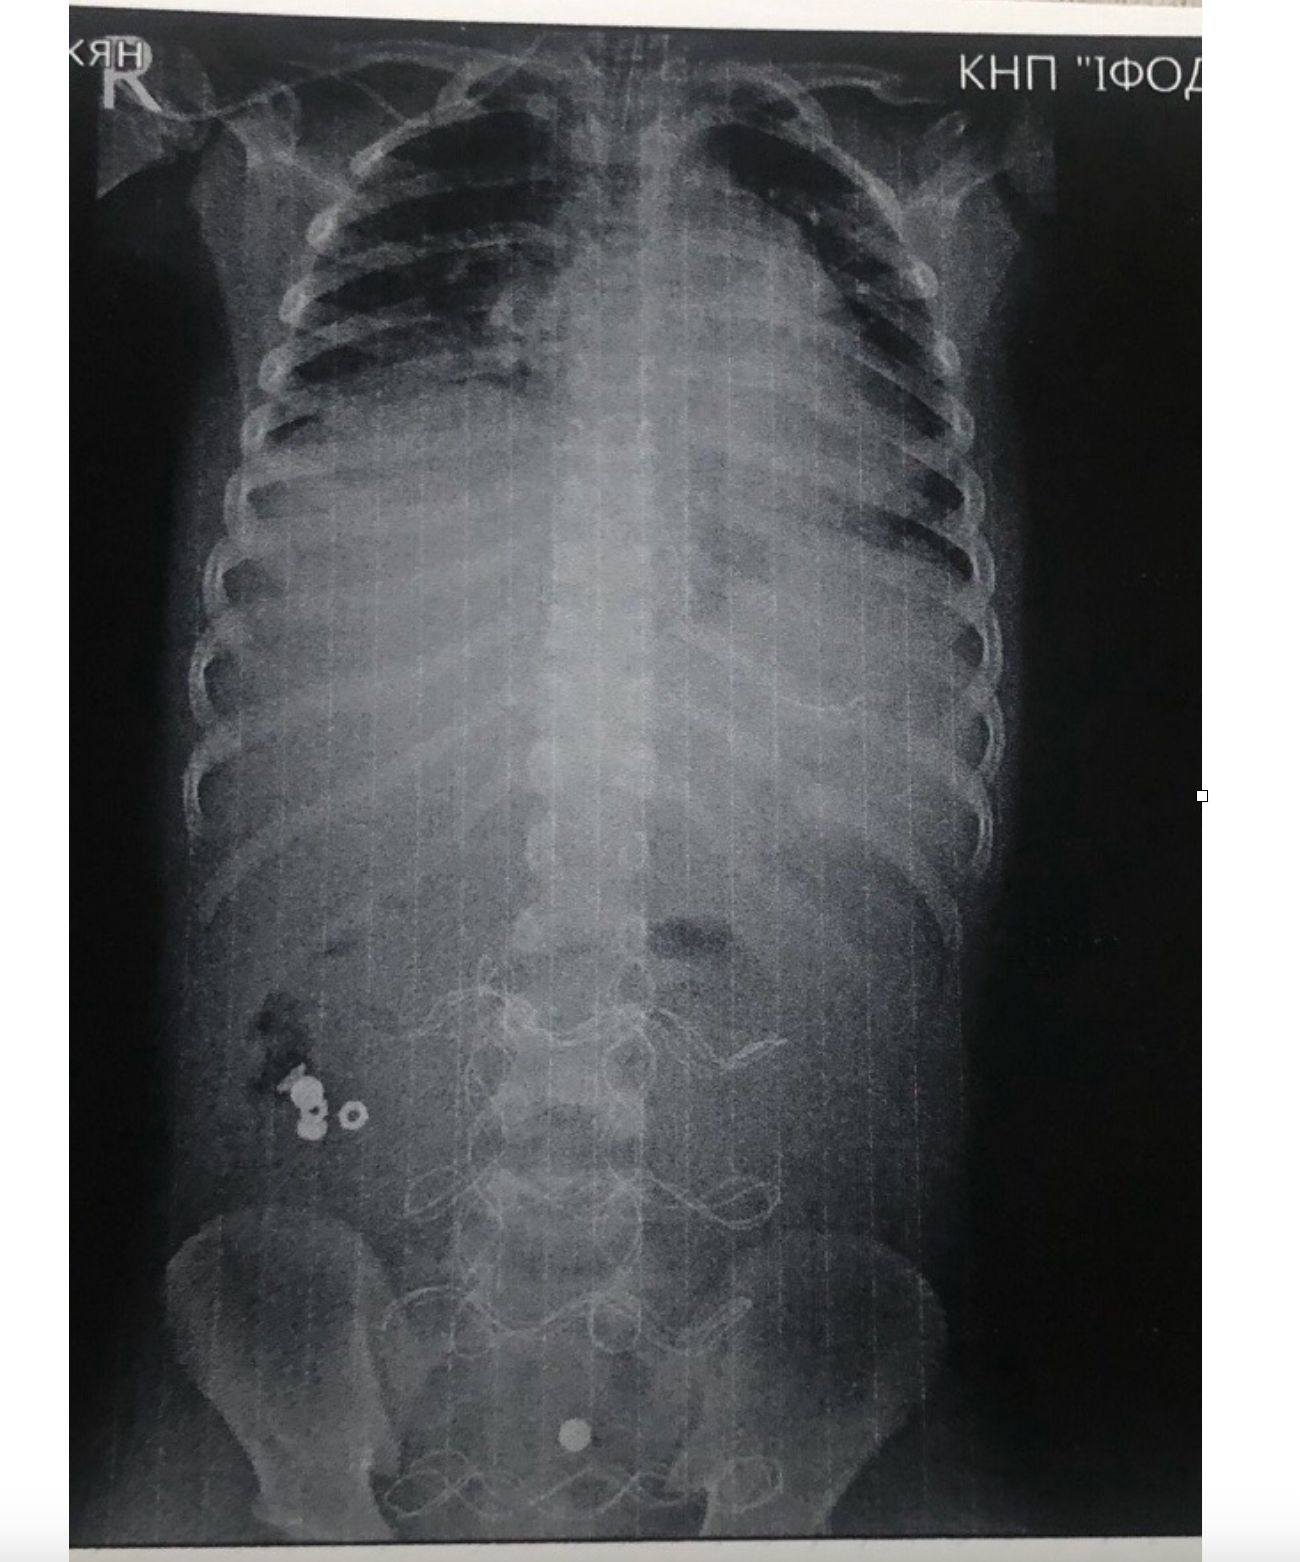

«12 годин тривала передопераційна підготовка. Всього було проведено три оперативні втручання і лише на 20 добу дитину було виписано в задовільному стані.Обов'язково поясніть дітям можливі наслідки ковтання батарейок, магнітів та інших об'єктів не призначених для цього», — йдеться у дописі.